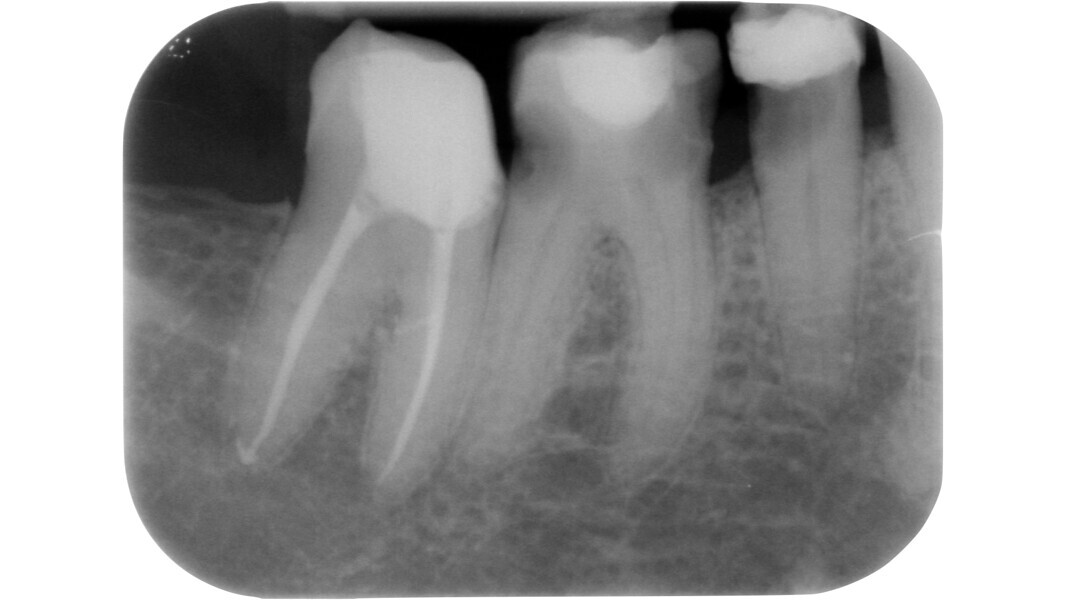

Fig. 15: Pre-op radiograph of a mandibular molar affected by irreversible pulpitis.

Fig. 16: Intermediate phase of treatment, after pre-endodontic reconstruction, access cavity preparation and preliminary canal shaping. Note the presence of a pulp stone on the floor of the chamber with a translucent appearance.

Fig. 17: Removal of the stone using a manual excavator.

Fig. 18: Stone removed.

Fig. 19: Appearance of the pulp chamber after obturation. Note the typical opacity of the floor without any calcification.

Fig. 20: Post-op radiograph.